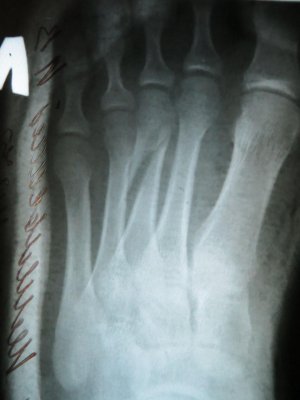

Сегодняшний рентгеновский снимок прилагаю.

• IMG_13 45.jpg

IMG_13 45.jpg

132,5 КБ · Просмотры: 720

• IMG_134 6.jpg

IMG_134 6.jpg

87,9 КБ · Просмотры: 638

По данному рентгеновскому снимку действительно показано оперативное лечение